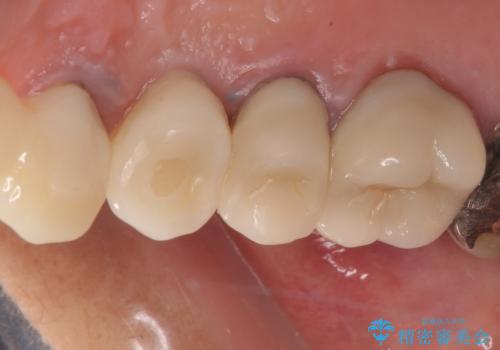

- 歯肉から膿が出てくるのが気になるとのことで来院された患者様です。

診察したところ、歯根に破折線が確認され抜歯が必要な状態でした。

歯肉や歯槽骨の状態は良好であったため、抜歯即時埋入インプラントによる補綴治療を行うこととしました。